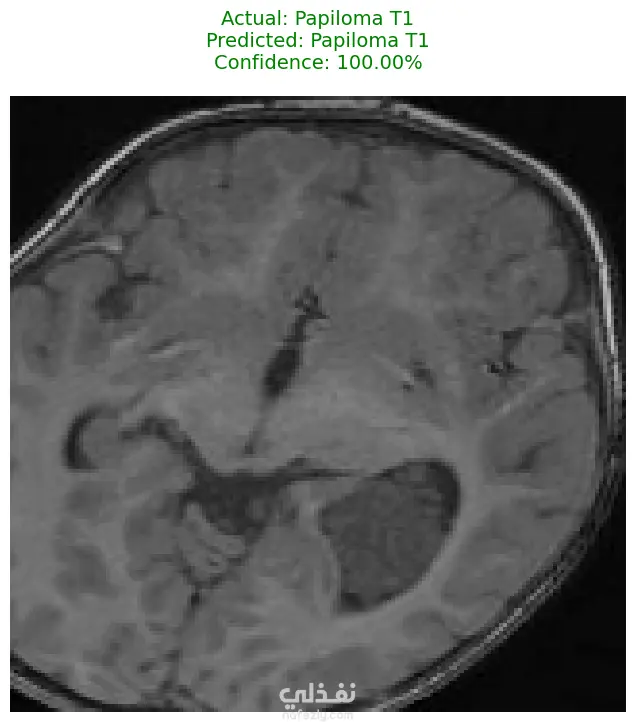

الوصف: قمت بتطوير نموذج تعلم عميق (CNN) قادر على التمييز بين 27 فئة مختلفة من الأورام والحالات الطبيعية بدقة تصل إلى 93%. شمل المشروع مراحل معالجة البيانات الضخمة، تنظيفها وموازنتها، وتصميم معمارية مخصصة لضمان الكفاءة العالية وتقليل استهلاك الذاكرة. المميزات التقنية: دقة استثنائية: حقق النموذج دقة تصل إلى 93% على بيانات التحقق (Validation Accuracy). معالجة البيانات الضخمة: تم العمل على قاعدة بيانات ضخمة، مع تطبيق استراتيجيات موازنة البيانات (Data Balancing) لضمان عدم انحياز الموديل. معمارية مخصصة: تم تصميم شبكة CNN تدعم تقنيات Batch Normalization لتسريع التعلم و Global Average Pooling لتقليل استهلاك الذاكرة وضمان استقرار النموذج. معالجة الصور: استخدام تقنيات OpenCV لقص الصور (Cropping) وإزالة الهوامش غير الضرورية لتركيز الموديل على منطقة الورم فقط. الأدوات والتقنيات المستخدمة: لغة البرمجة: Python. المكتبات الأساسية: TensorFlow / Keras. معالجة الصور: OpenCV & PIL. تحليل النتائج: Scikit-learn (Confusion Matrix & Classification Report). البيئة البرمجية: Google Colab (GPU Acceleration). النتائج المحققة: نموذج قادر على التعرف على أنواع نادرة من الأورام بدقة عالية. تقرير فني يوضح أداء الموديل لكل فئة (Precision & Recall). ملف نموذج جاهز للنشر (Deployment) بصيغة keras الحديثة. يمكنكم الاطلاع على الكود المصدري كاملاً والرسوم البيانية لتقييم أداء النموذج عبر رابط GitHub المرفق، كما يتوفر رابط تحميل النموذج المدرب داخل ملف الشرح.